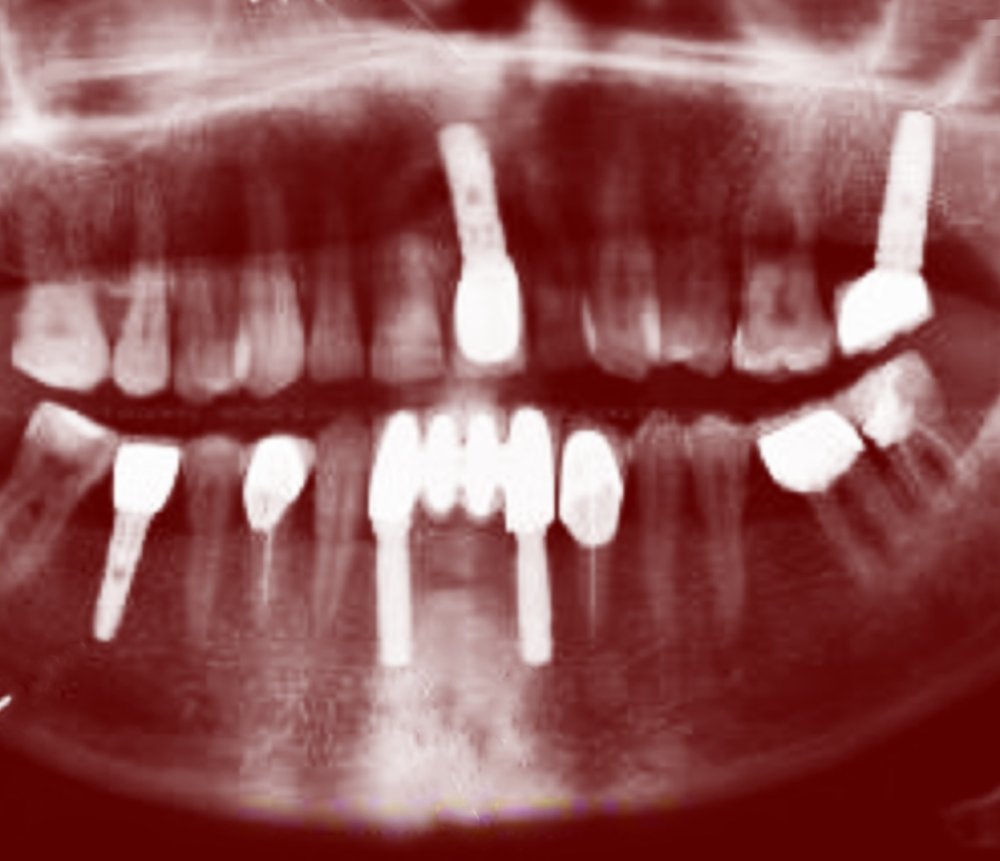

AYRIK DİŞ

2018